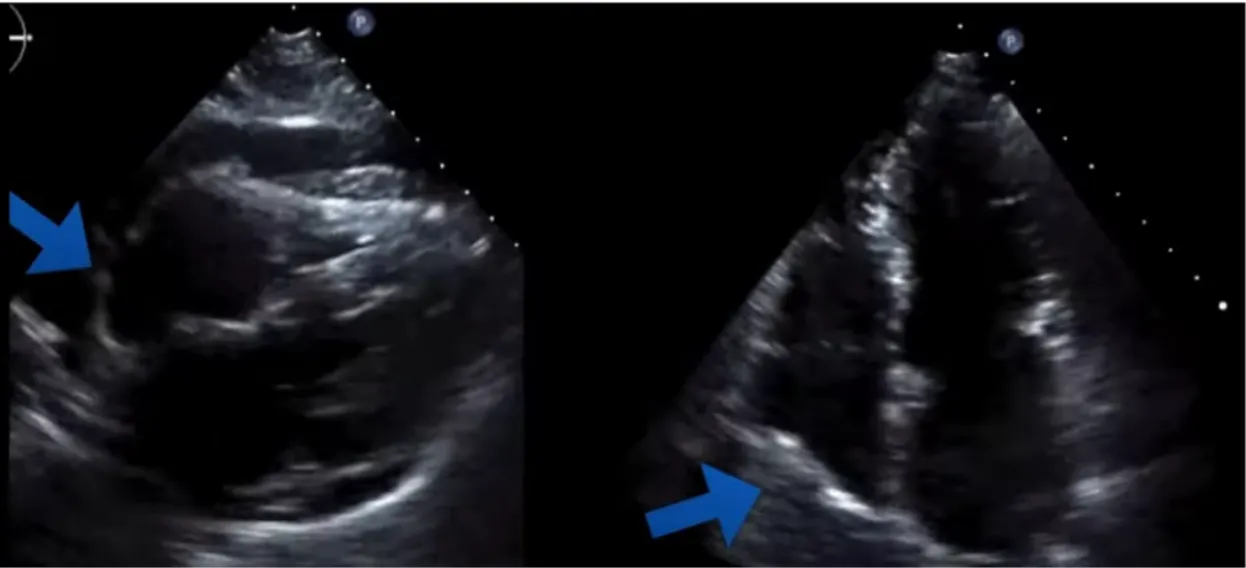

Long axis에서 RV free wall이 diastolic collapse 있는지 . 특히 early diastolic때

Early diastolic 때 venous return 이 가장 적은 상태에서 RV pressure 가 가장 적어 collapse 되었다가 Late diastolic( atrial kicking) 때 RV pressure 올라가서 다시 dilatation

HR빠르면 평가 어려움->M mode

Early diastolic timing은 EKG상 T wave 이용하여 보는 방법(T wave끝)도 있겠으며 valve가 열리는 timing 을 보고 early diastolic 을 판단하는 것도 가능.

MV 열리는 시점이 diastole. 이때 RV free wall이 collapse하는 것 보임.

DC: diastolic Collapese